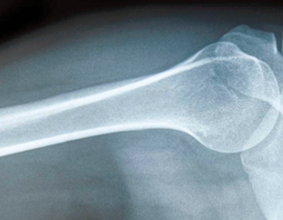

明明追问道:“骨头是不是白色的呢?”妈妈回答道:“对,所以骨折或者骨质增生的辅助检查,首选X光。”